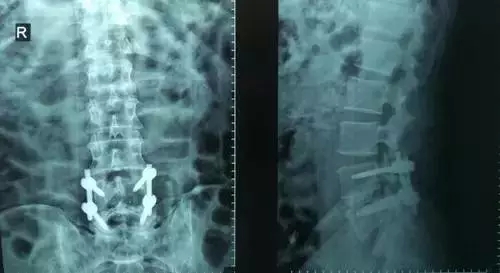

劉志安副院長(zhǎng)所說(shuō)的“微創(chuàng)小切口”就是通道下髓核摘除植骨融合經(jīng)皮內(nèi)固定術(shù)。其原理就是利用MIS-TLIF技術(shù)微創(chuàng)治療腰椎疾病,不但能達(dá)到開(kāi)放手術(shù)的效果,且切口及創(chuàng)傷為開(kāi)放切口的1/3,術(shù)中出血量少,患者術(shù)后可以恢復(fù)更快。

劉志安副院長(zhǎng)將具體的手術(shù)過(guò)程向朱先生做了介紹,朱先生也同意了這個(gè)“微創(chuàng)小切口”手術(shù)。于是在術(shù)前的精心準(zhǔn)備之后,劉志安副院長(zhǎng)協(xié)同其他醫(yī)護(hù)人員為朱先生進(jìn)行了手術(shù)。術(shù)后,朱先生的切口愈合良好,腰部疼痛消失,小腿麻木感也漸漸緩解。“手術(shù)后傷口略微有點(diǎn)痛,現(xiàn)在已經(jīng)完全不痛了,這種輕松的感覺(jué)已經(jīng)好久沒(méi)有了,真是萬(wàn)分感謝劉院長(zhǎng)。”在病房?jī)?nèi),一臉笑容的朱先生如是說(shuō)。

據(jù)劉院長(zhǎng)介紹,MIS-TLIF技術(shù)是經(jīng)椎旁肌間隙入路運(yùn)用脊柱內(nèi)鏡或?qū)S猛ǖ佬醒甸g盤(pán)切除、椎管減壓、植骨內(nèi)固定術(shù),是一項(xiàng)應(yīng)用廣泛、技術(shù)成熟的脊柱微創(chuàng)手術(shù)方法。本技術(shù)可以完成與傳統(tǒng)手術(shù)完全相同的椎間盤(pán)切除、椎間植骨融合內(nèi)固定等操作。手術(shù)切口一般3-5厘米,本手術(shù)方式可有效避免傳統(tǒng)手術(shù)對(duì)腰背肌肉的損傷,患者術(shù)后腰背部疼痛輕、恢復(fù)快,手術(shù)效果優(yōu)于傳統(tǒng)手術(shù),治療后1-3天即可下床活動(dòng)。本技術(shù)適于大部分的腰椎間盤(pán)突出癥、腰椎管狹窄癥、腰椎滑脫癥等。